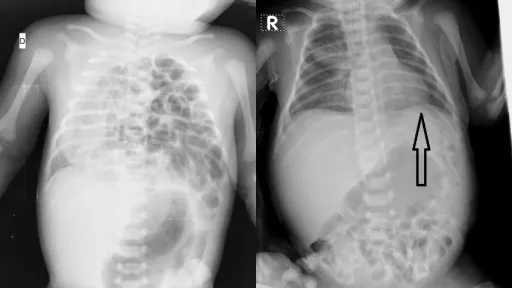

Cu ajutorul toracoscopiei s-a reușit reducerea parţiala a anselor în cavitatea abdominală, prin defectul diafragmatic, totodată fiind confirmată hipoplazia plămânului stâng. Ținând cont de malrotația intestinală prezentă, s-a recurs la laparotomie subcostală pe stânga cu reducerea anselor în cavitatea abdominală, amplasarea lor în poziție anatomică şi realizarea plastiei defectului hemidiagrafmului stâng prin abord abdominal, intervenția fiind video asistată toracoscopic.

După operație: intestinele sunt readuse în cavitatea abdominală, iar defectul diafragmatic este înlăturat.